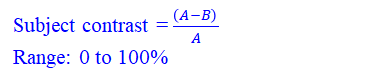

对比度

对比度是指图像上的差异、灰度之间紧密相邻图像上的区域。

对比度的分类:

1)对象本身得对比度

2)探测器(胶片或采集系统)的对比

3)显示成像的对比(给医生看的屏幕对比度怎么样)

X光穿过人体,如骨头吸收的多或者厚的组织吸收的X光多一点,薄的或者如空气、水等吸收X光少一点,则就会出现差别,它们的吸收率(吸收X光的强度)不一样,吸收率公式如下: